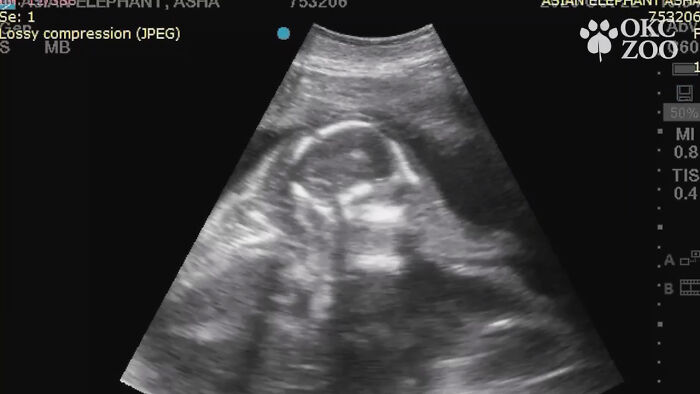

While the world was preoccupied with the coronavirus pandemic back then, a zoo in Oklahoma shared an ultrasound of a baby elephant that made the world stop for a second and all go aww.

Remember the baby elephant ultrasound everyone was talking about back in late November of 2020?

Rama (meaning “pleasing” in Sanskrit) the Asian elephant first came up on the internet radar back in late November of 2020, when Oklahoma City Zoo announced its beloved then 25-year-old mommy elephant Asha, now 26 years of age, was pregnant.

The announcement was made when Asha was 8 months pregnant—that is 8 of the 22 total months (about 660 days) elephant pregnancies last. The original prognosis was sometime in February, 2022, which back then felt like a long way away, but here we are. Rama was born on January 20, 2022, at 8:26 p.m., inside the Zoo’s elephant barn at Sanctuary Asia.